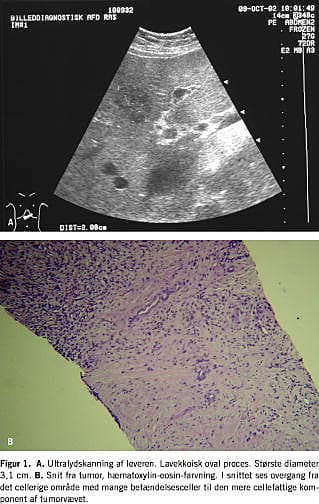

Ved klinisk undersøgelse blev der ikke fundet hepatomegali. Ved ultralydskanning af abdomen sås en ca. 3 cm stor lavekkoisk proces lateralt i venstre leverlap, som umiddelbart blev tolket som metastasesuspekt (Figur 1 ). Ductus choledochus fandtes antydningsvis ektatisk og målte 8 mm i diameter. Patienten blev herefter henvist til organkirurgisk afdeling til videre udredning.

Ved ultralydskanning af abdomen ses IPL som en solitær homogen lavekkoisk læsion i leverparemkymet. Ved computertomografi ses kontrastopladning.